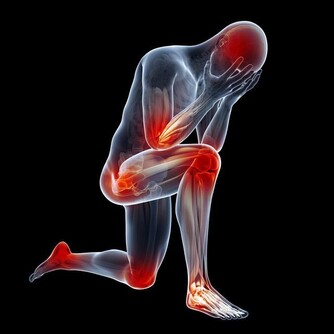

1、靜脈曲張和靜脈血栓患者

熱水泡腳時,下肢動脈擴張,尤其表現為皮膚充血,更多的動脈血液進入下肢。

然而,靜脈的回流能力並不會因此增加;於是,熱水泡腳對於本來回流不暢或阻塞的靜脈病患者來講,會加重血液淤積;此外熱水泡腳,還可以導致毛細血管破裂,形成皮膚上的出血點;時間久了,就會形成色素沉著,小腿顏色變黑。